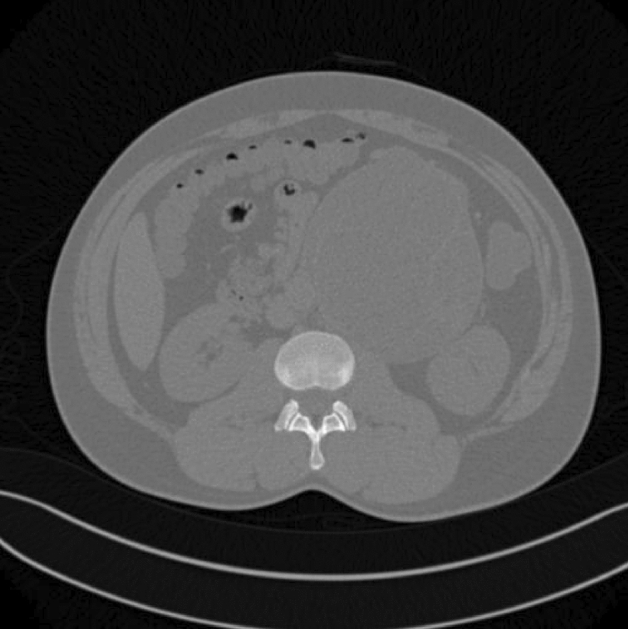

Methods and procedures: An 81-year-old Caucasian female was admitted to the emergency room with a complaint of 24-h epigastric pain, associated with nausea. She had history of a laparoscopic reduction of the foramen of Winslow internal hernia in our institution. CT scan of her abdomen showed a lesser sac internal hernia with an incarcerated colon and underwent a laparoscopic repair with a flap of falciform ligament and laparoscopic cecopexy. The surgery was successful.

Results: Foramen of Winslow hernias, a rare type of internal hernia. Internal hernias have an incidence rate of less than one percent, with Foramen of Winslow hernias accounting for only 8% of all internal hernias. The case at hand involves an 81-year-old Caucasian women who described a prior history of hypertension and a past laparoscopic reduction of the Foramen of Winslow internal hernia in the past. She had complaints of 24-h epigastric pain associated with nausea. She underwent a CT scan of her abdomen which revealed a lesser sac internal hernia with an incarcerated colon and was taken to the operating room where her Foramen of Winslow internal hernia was repaired laparoscopically using a flap of falciform ligament. The hernia contents included the ascending colon and ileum and were viable. A laparoscopic cecopexy and a flap of falciform ligament were done. The surgery was successful.